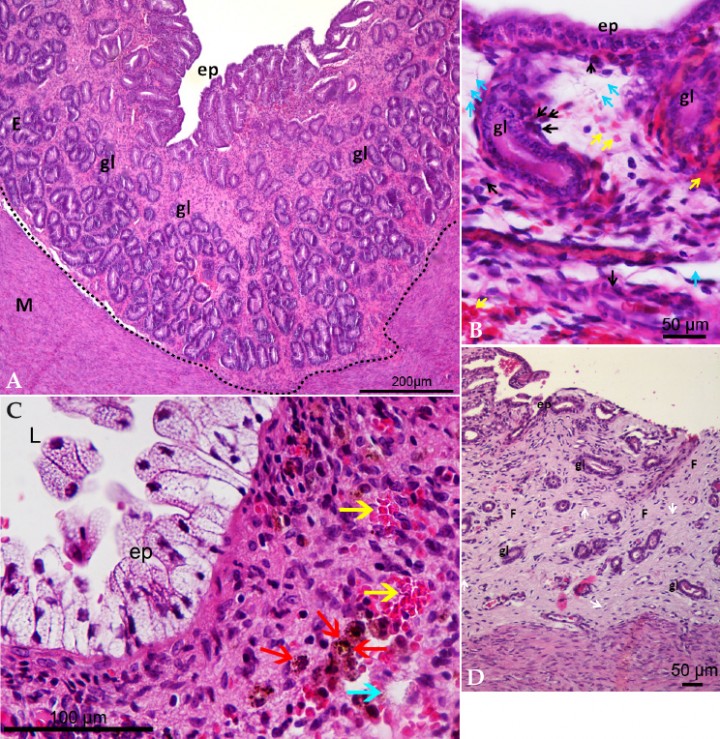

El endometrio normal presenta epitelio cilíndrico simple y lámina propia con tejido conjuntivo y con glándulas endometriales (Fig. 1A). En la EH, el examen histopatológico permite observar cambios inflamatorios como infiltración de células inflamatorias, hiperemia y congestión vascular, hemorragia y edema en el estroma.[ Bondurant RH: Inflammation in the bovine female reproductive tract. J Anim Sci 1999; 77:101-110. [pubMed] , McEntee K: The female genital system. En Jubb KVF, Kennedy PC, Palmer N (ed): Pathology of domestic animals. Academic Press, Orlando, FL, 1983; 305-407. , DeBois C, Manspeaker J: Endometrial biopsy of the bovine. En Morrow DA (2nd ed): Current Therapy in Theriogenology, Philadelphia, PA, WB Saunders Co; 1986; 424-427. ] Asimismo, considerando el curso de la inflamación podemos clasificar a la EH en aguda (Fig. 1B), subaguda (Fig. 1C) y crónica (Fig. 1D). En la EH aguda se observa moderada a severa hiperemia y/o congestión, hemorragia, así como un infiltrado celular inflamatorio difuso (polimorfonucleares neutrófilos; PMNN). En la EH subaguda se observa hiperemia y/o congestión moderada a severa, hemorragia junto con un infiltrado celular inflamatorio en el que, además de neutrófilos, se observan linfocitos y macrófagos con o sin hemosiderina. Por último, en la EH crónica se observa presencia de linfocitos y macrófagos, hiperplasia de tejido conectivo, en ocasiones con atrofia de las glándulas endometriales, leve a moderada hiperemia y/o congestión.[ Praderio R. Endometritis subclínica en la perra. Tesis doctoral. Facultad de Ciencias Veterinarias, Universidad Nacional de La Plata. 2019. , Schlafer DH: Diseases of the Canine Uterus. Reprod Dom Anim 2012; 47: 318-322. [pubMed] , Gifford AT, Scarlett JM, Schlafer DH: Histopathologic findings in uterine biopsy samples from subfertile bitches: 399 cases (1990-2005). J Am Vet Med Assoc 2014; 244: 180-186. [pubMed] ] Macroscópicamente, en la EH el útero no evidencia lesiones.[ Praderio RG, García Mitacek MC, Nuñez Favre R, et al.: Uterine endometrial cytology, biopsy, bacteriology, and serum C-reactive protein in clinically healthy diestrus bitches. Theriogenology 2019; 131: 153-161. [pubMed] ] A partir de la realización de estudios previos sobre endometrio canino se ha hipotetizado que, como afección endometrial que modifica el medioambiente uterino, la EH se relaciona con fallo en la implantación, lo que se asocia a infertilidad o subfertilidad y se ve reflejado en las pérdidas de preñeces, dando como resultado perras vacías o con menores tamaños de camada.[ Fontaine E, Levy X, Grellet A, et al.: Diagnosis of endometritis in the bitch: a new approach. Reprod Dom Anim 2009; 44: 196-199. [pubMed] , Praderio R. Endometritis subclínica en la perra. Tesis doctoral. Facultad de Ciencias Veterinarias, Universidad Nacional de La Plata. 2019. , Gifford AT, Scarlett JM, Schlafer DH: Histopathologic findings in uterine biopsy samples from subfertile bitches: 399 cases (1990-2005). J Am Vet Med Assoc 2014; 244: 180-186. [pubMed] ]

<p>(<strong>A</strong>) Microfotografía de biopsia uterina teñida con hematoxilina y eosina. Endometrio normal de perra. Epitelio de superficie (ep), glándulas endometriales (gl), endometrio (E), miometrio (M). (X100, H&E). (<strong>B</strong>) Microfotografía de biopsia uterina teñida con hematoxilina y eosina. Endometritis histológica aguda. Epitelio de superficie (ep), glándulas endometriales (gl). Las flechas negras marcan neutrófilos, las flechas amarillas marcan glóbulos rojos y las flechas celestes marcan edema. (X600, H&E). (<strong>C</strong>) Microfotografía de biopsia uterina teñida con hematoxilina y eosina. Endometritis histológica subaguda. Epitelio de superficie (ep), lumen (L). Las flechas amarillas marcan glóbulos rojos, las flechas celestes marcan edema y las flechas rojas marcan hemosiderina. (X600, H&E). (<strong>D</strong>) Microfotografía de biopsia uterina teñida con hematoxilina y eosina. Endometritis histológica crónica. Epitelio de superficie (ep), glándulas endometriales (gl), fibrosis (F). Las flechas blancas marcan fibrocitos. (X100, H&E).</p>

(A) Microfotografía de biopsia uterina teñida con hematoxilina y eosina. Endometrio normal de perra. Epitelio de superficie (ep), glándulas endometriales (gl), endometrio (E), miometrio (M). (X100, H&E). (B) Microfotografía de biopsia uterina teñida con hematoxilina y eosina. Endometritis histológica aguda. Epitelio de superficie (ep), glándulas endometriales (gl). Las flechas negras marcan neutrófilos, las flechas amarillas marcan glóbulos rojos y las flechas celestes marcan edema. (X600, H&E). (C) Microfotografía de biopsia uterina teñida con hematoxilina y eosina. Endometritis histológica subaguda. Epitelio de superficie (ep), lumen (L). Las flechas amarillas marcan glóbulos rojos, las flechas celestes marcan edema y las flechas rojas marcan hemosiderina. (X600, H&E). (D) Microfotografía de biopsia uterina teñida con hematoxilina y eosina. Endometritis histológica crónica. Epitelio de superficie (ep), glándulas endometriales (gl), fibrosis (F). Las flechas blancas marcan fibrocitos. (X100, H&E).

Con el fin de estudiar e identificar cambios del endometrio que nos permitan diagnosticar afecciones endometriales, es preciso definir cuál es la imagen histológica normal del endometrio canino. El endometrio normal presenta pliegues longitudinales de mucosa, epitelio columnar simple intacto en la superficie endometrial y tejido conjuntivo formando la lámina propia con glándulas endometriales de estructura conservada (Fig. 1A).